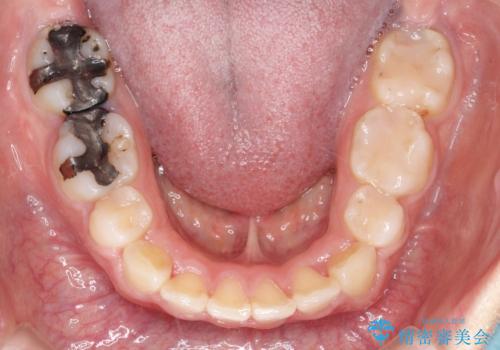

上下左右小臼歯を抜歯して審美装置で治療を行いました。

抜歯したスペースをきちんと下げることができるように、矯正用のアンカースクリューを用いて治療をしております。